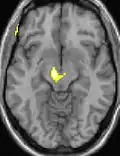

Positron emission tomography (PET) scans indicate the brain areas which are activated during attack only, compared to pain free periods. These pictures show brain areas that are active during pain in yellow/orange color (called "pain matrix"). The area in the center (in all three views) is activated only during cluster headaches. The bottom row voxel-based morphometry shows structural brain differences between individuals with and without CH; only a portion of the hypothalamus is different.[36]